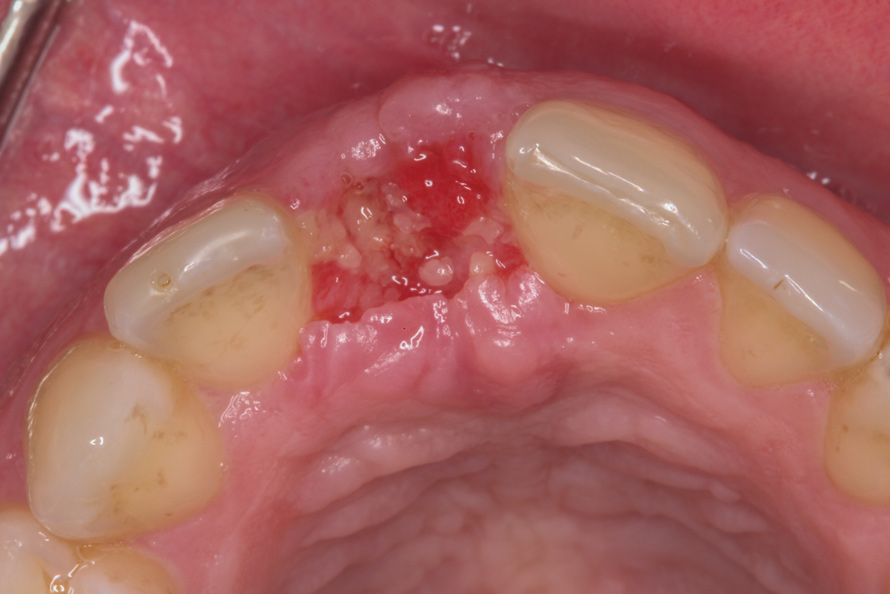

The patient was scheduled for weekly postoperative assessments. The barrier was removed after 5 weeks using a college plier without anesthetizing the patient. After the barrier was removed, osteoid tissue (red connective tissue) was seen covering the bone graft, as anticipated (Figure 9). If bone graft particles are present at the extraction site, they can be left in place, as connective tissue will cover them within 1 to 2 weeks. The epithelium creeps across the reddish connective tissue, and the site becomes pinkish in approximately 2 weeks, as occurred in this case (Figure 10).6

Fig 9. Wound healing was evident immediately after d-PTFE barrier removal. Red osteoid tissue was present.

Figure 9

Fig 10. At 7 weeks follow-up, keratinized tissue was present.

Figure 10